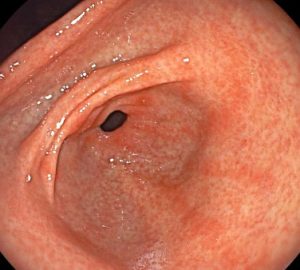

La gastritis es la inflamación del revestimiento del estómago. Puede ser aguda, que es de corta duración, o crónica, cuando persiste durante un período prolongado. La causa más común de gastritis es una infección bacteriana por Helicobacter pylori, aunque también puede ser causada por el uso excesivo de medicamentos antiinflamatorios no esteroideos (AINEs), consumo excesivo de alcohol, estrés, fumar, trastornos autoinmunes u otras enfermedades.